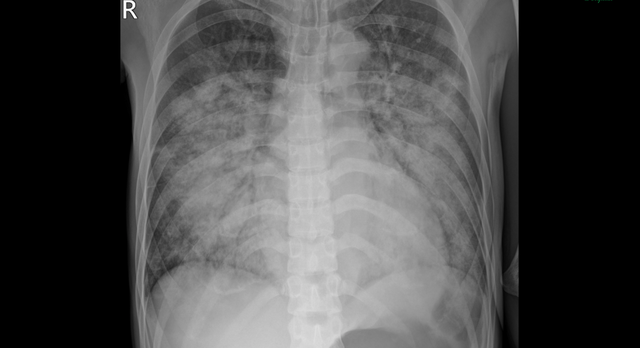

Phim chụp X quang thể hiện tổn thương mờ, lan tỏa 2 phổi của bệnh nhân. Ảnh: BVCC

Kết quả chẩn đoán cho thấy bệnh nhân bị suy tim cấp nặng, chức năng co bóp cơ tim suy giảm nghiêm trọng, chỉ còn 31%. Tình trạng này đi kèm Nhiễm trùng máu và viêm phổi nặng, khiến suy hô hấp tiến triển nhanh, nguy cơ tử vong cao.